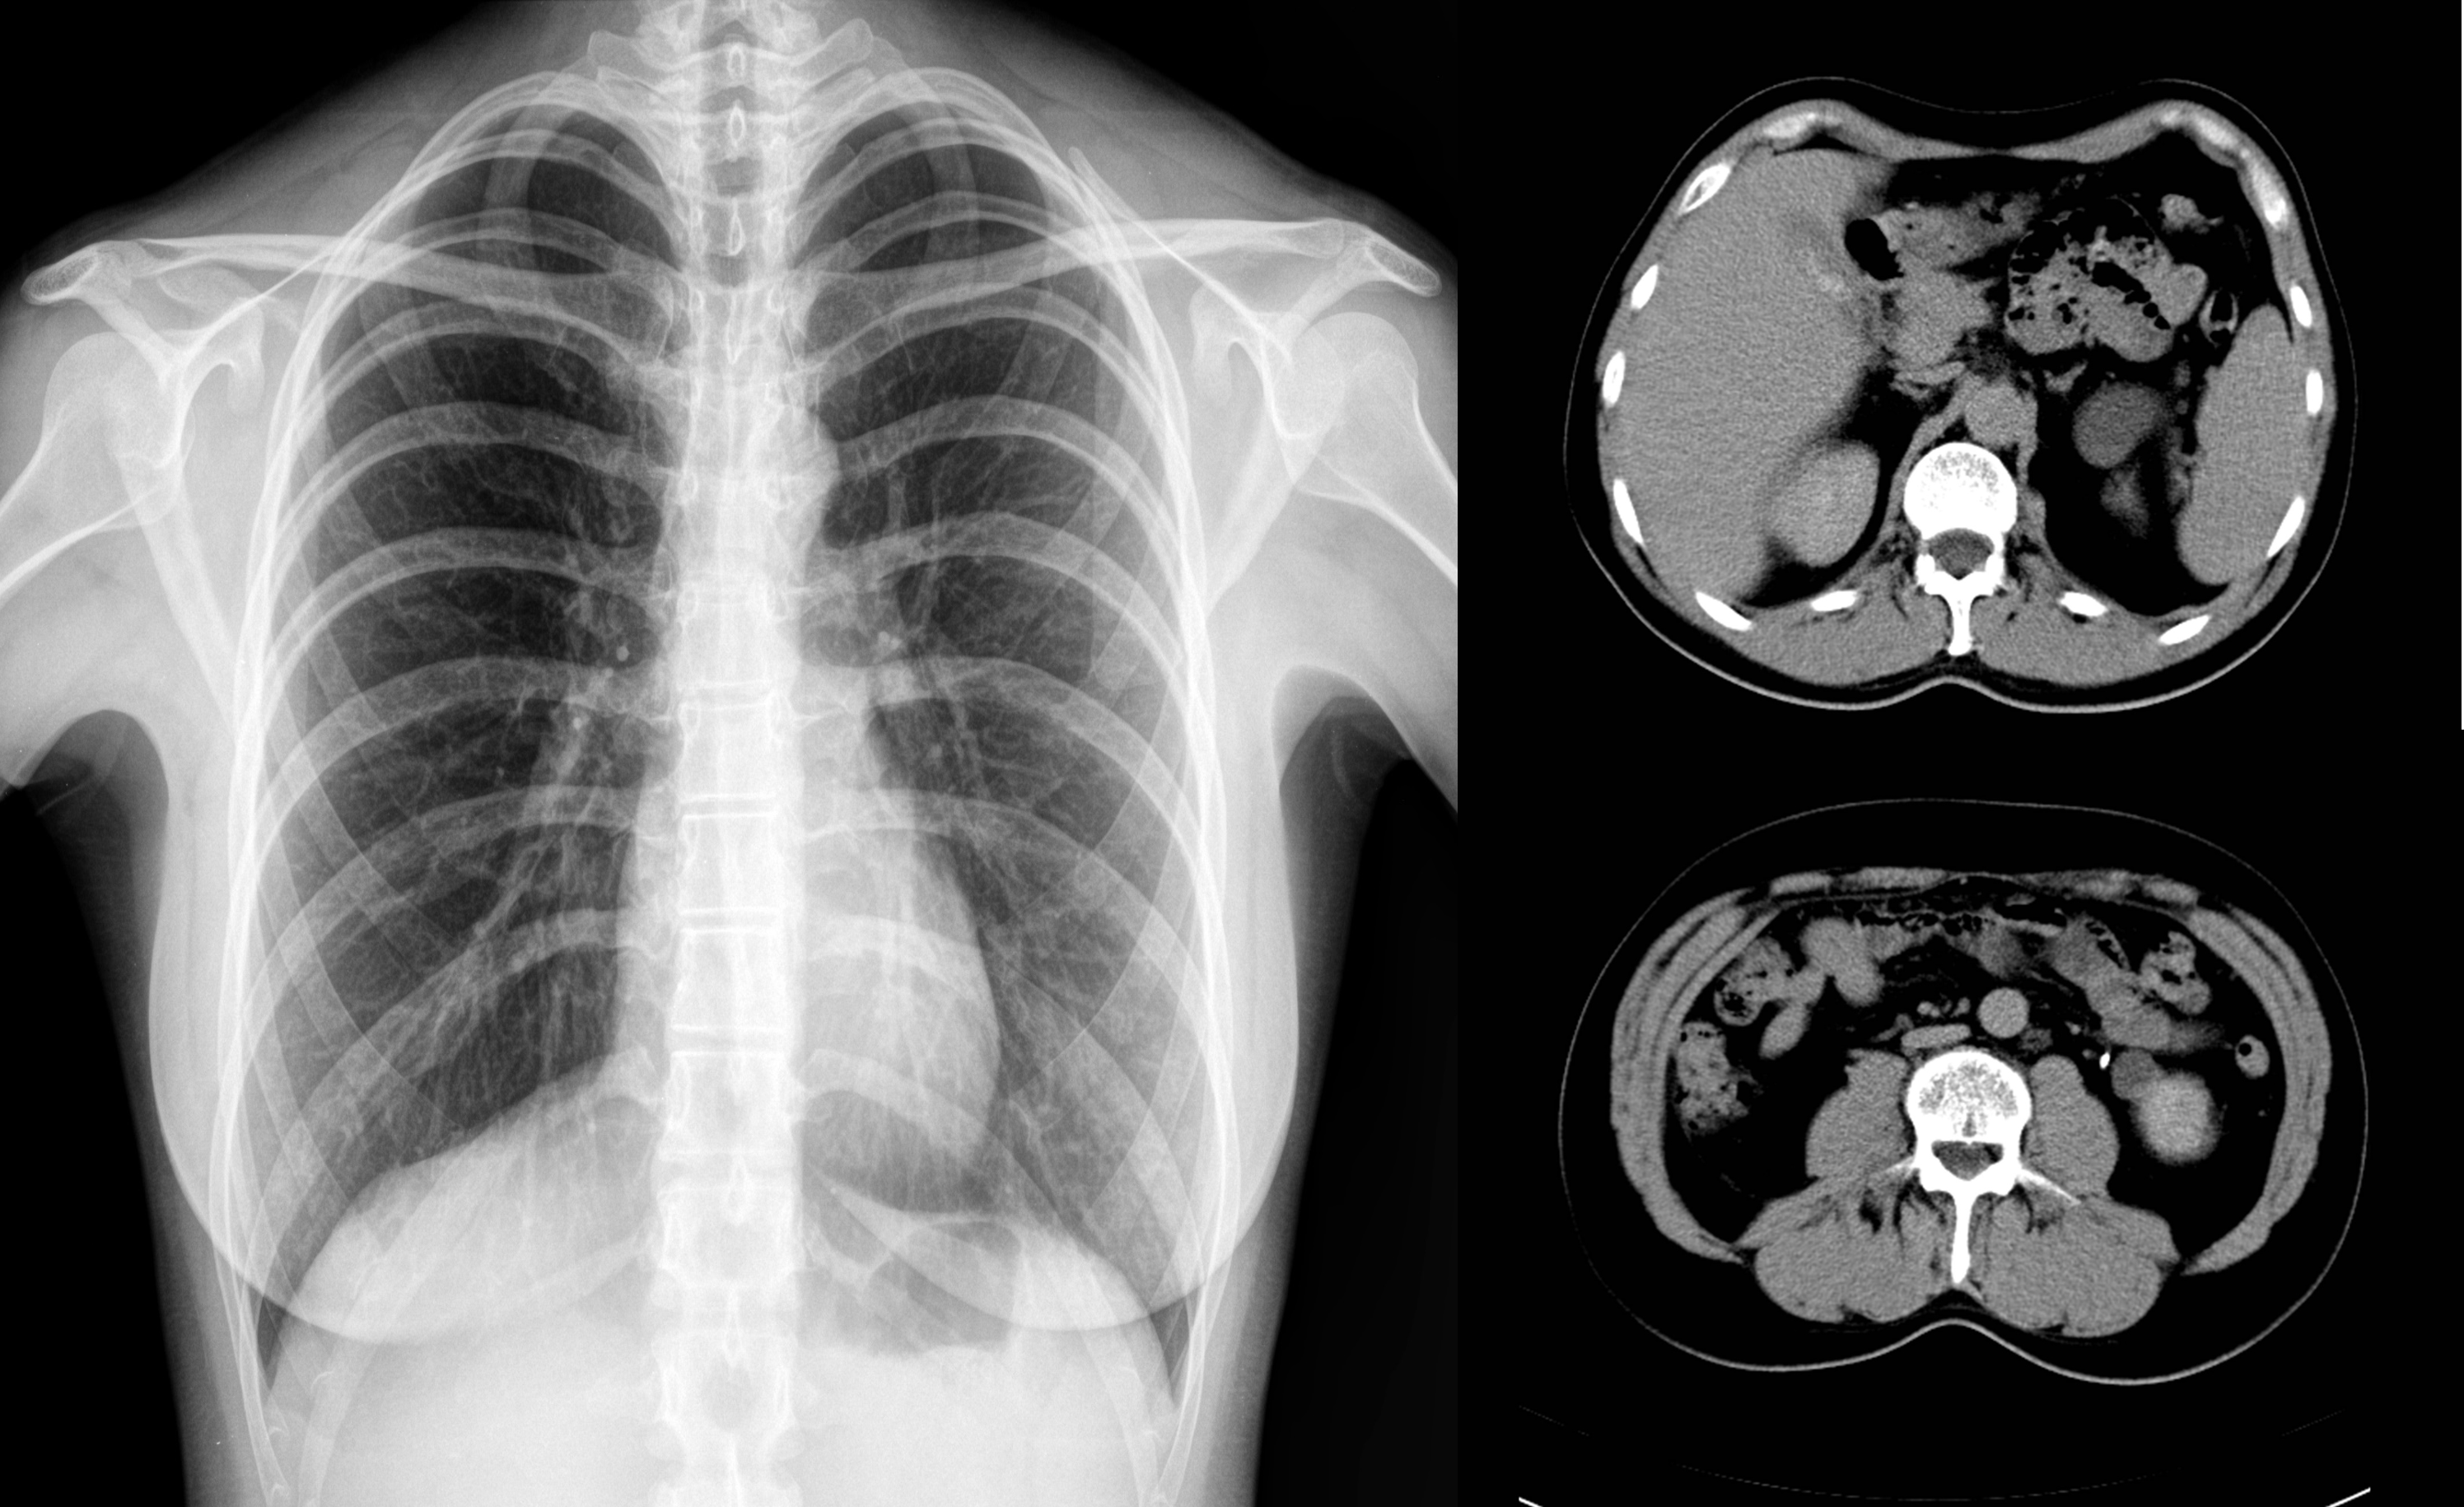

Of course, it happens. Patients with suspected pneumonia or suspected fractures may require X-ray or CT. In this case, the abdomen in which the fetus is located is covered with a shield which prevents the radiation. Especially for non-abdominal examinations, the radiation exposure of the fetus is insignificant. If the stomach is sore and needs inspection, we use ultrasound or MRI without radiation. If you tell that you are pregnant, the inspection is always carried out in consideration of radiation.